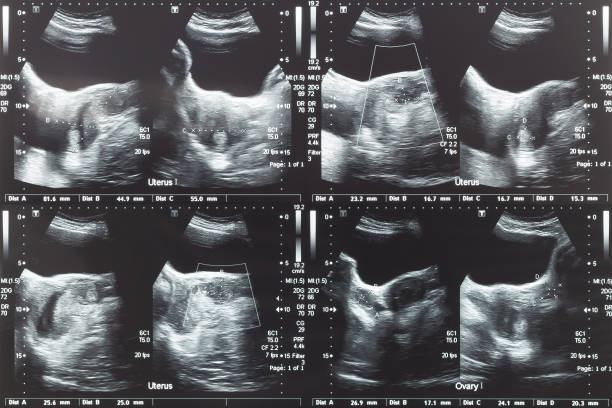

자궁근종(Uterine fibroids)은 여성의 자궁 내에 발생하는 양성 종양으로, 자궁 내막이나 근층에서 생길 수 있습니다. 대부분의 경우, 이 종양은 악성 종양이 아니며, 치료하지 않아도 괜찮은 경우가 많습니다. 그러나 증상이 심한 경우, 치료가 필요할 수 있습니다. 자궁근종의 증상은 그 크기와 위치에 따라 다릅니다. 아무런 증상이 없는 경우도 있지만, 대개는 다음과 같은 증상을 보일 수 있습니다.

위와 같은 증상이 나타날 경우 의사와 상담하여 적절한 치료 방법을 선택해야 합니다. 치료 방법은 자궁근종의 크기, 위치, 증상 등에 따라 달라질 수 있으며, 대개의 경우 증상 완화와 근종 크기 축소를 위해 치료를 시도합니다.

자궁근종의 치료 방법으로는 약물 치료, 수술, 비침습적 절제술 등이 있습니다. 약물 치료는 자궁근종의 크기를 축소시키는 목적으로 사용되며, 경구 투여나 주사 등으로 적용될 수 있습니다. 수술은 자궁근종을 제거하는 수술로 대개 자궁 축소술이나 자궁적출술 등이 사용됩니다. 비침습적 절제술은 자궁근종의 혈액 공급을 차단하여 근종 크기 축소를 유도하는 방법으로, 자궁동맥동결술, 초음파 유도하 고강도 집속초음파(자궁동맥소작술), 대동맥 삽입술 등이 사용됩니다.